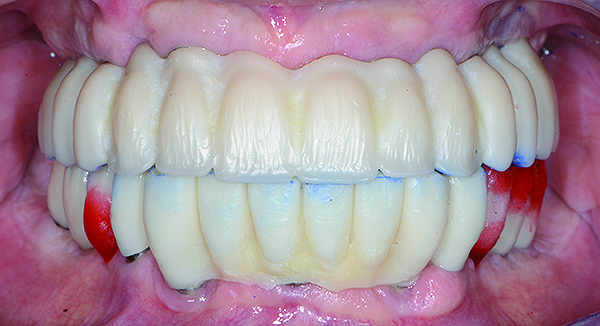

The maxillary prototype was adjusted, polished, and left to function with the mandibular provisional. The definitive maxillary zirconia restoration was then completed from the information provided by the prototype, and the cutbacks for the facial porcelain (Nos. 6 through 11) were done after milling but before sintering. Subsequently, the mandibular prototype was adjusted to the sintered and colored maxillary zirconia framework before the application of porcelain to Nos. 6 through 11 and final glazing (Figure 11). Following this step, the mandibular definitive monolithic zirconia restoration was milled, colored, and sintered. The facial porcelain (Nos. 6 through 11) was applied, and then both maxillary and mandibular restorations were stained and glazed (Figure 12). Both bridges were inserted at the same time (Figure 13 through Figure 15). Minor occlusal adjustments and oral hygiene access was verified and the zirconia surfaces polished. The bridge screws were torqued to 20 Ncm according to the manufacturer’s recommendation, and No. 24 was luted with a provisional cement. Postoperative radiographs were taken (Figure 16).

Fig 11. Intraoral frontal view of the maxillary zirconia restoration and adjusted mandibular PMMA prototype.

Figure 11

Fig 12. Extraoral frontal view of the completed maxillary and mandibular articulated zirconia restorations on master casts.

Figure 12